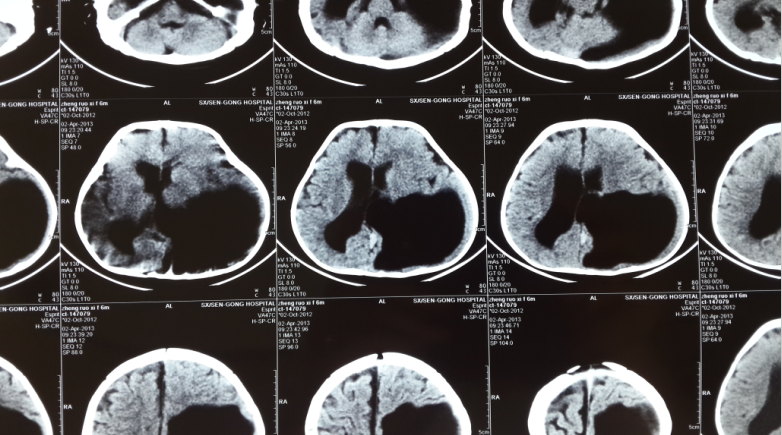

脑梗还是脑穿通畸形

鉴别诊断:开放型脑裂畸形应与脑穿通畸形囊肿鉴别,最关键点是开放型脑

明显占位效应,相邻脑实质有受压改变,脑穿通畸形囊肿占位效应常不明显

(先天性第四脑室中,侧孔闭锁综合征)脑裂畸形(灰质)脑穿通畸形(白质)